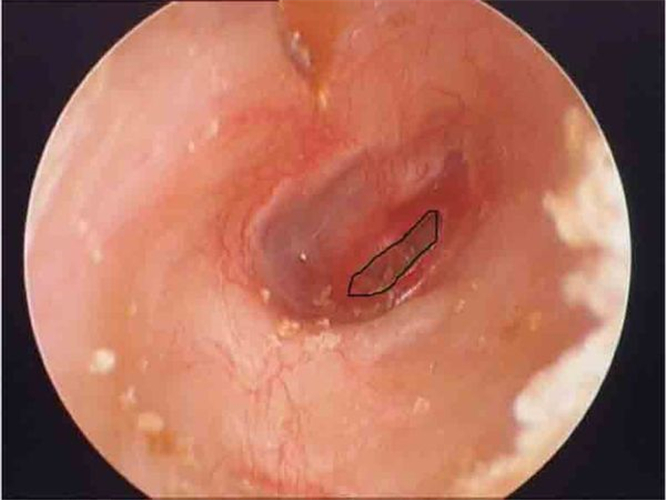

外傷性破裂鼓膜穿孔